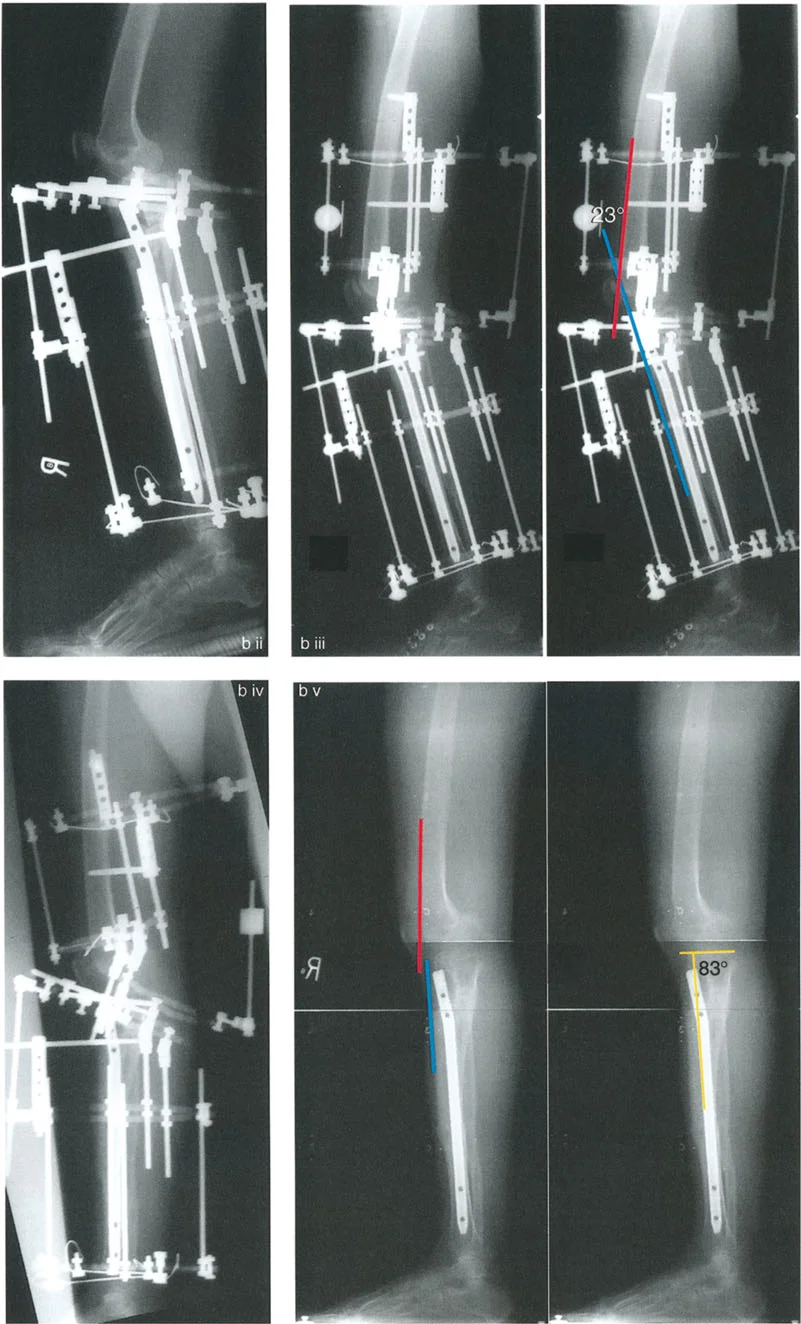

- تقييم مدى الحركة: يتم قياس مدى حركة الركبة، بما في ذلك أقصى تمدد وأقصى انثناء. يتم تحديد درجة فرط التمدد (HE - Hyperextension) أو درجة تقلص الانثناء الثابت (FFD - Fixed Flexion Deformity).

زوايا القياس الهامة:

- زاوية الانحناء البعيدة للفخذ (PDFA - Posterior Distal Femoral Angle): تقيس زاوية الجزء السفلي من عظم الفخذ. القيمة الطبيعية حوالي 84 درجة. الزيادة في هذه الزاوية (أكثر من 84 درجة) تشير إلى ارتداد فخذي.

- زاوية الانحناء القريبة للظنبوب (PPTA - Proximal Posterior Tibial Angle): تقيس زاوية الجزء العلوي من عظم الساق. القيمة الطبيعية حوالي 80 درجة. الزيادة في هذه الزاوية (أكثر من 80 درجة) تشير إلى ارتداد ظنبوبي.

- مركز دوران الزاوية (CORA - Center of Rotation of Angulation): يتم تحديد هذا النقطة على الأشعة السينية لتحديد مكان التشوه العظمي بدقة، وهو أمر بالغ الأهمية لتخطيط عملية قطع العظم.

2. العلاج الجراحي: قطع العظم (Osteotomy)

الهدف من جراحة قطع العظم هو إعادة محاذاة العظام وتصحيح التشوه الزاوي في المستوى السهمي، لاستعادة وظيفة الركبة الطبيعية واستقرارها.

أ. قطع العظم الفخذي لتصحيح الارتداد الفخذي:

- متى يتم إجراؤها: عندما يكون التشوه الرئيسي في عظم الفخذ البعيد.

- الإجراء: يتم إجراء قطع للعظم (عادة قطع عظم انثناء) في الجزء البعيد من عظم الفخذ، عند مركز دوران الزاوية (CORA)، لإعادة محاذاة العظم.

- الهدف: تصحيح فرط تمدد الركبة واستعادة المحاذاة الطبيعية.

- مثال: لتصحيح ارتداد فخذي بمقدار 20 درجة، يتم إجراء قطع عظم انثناء فخذي بمقدار 20 درجة.